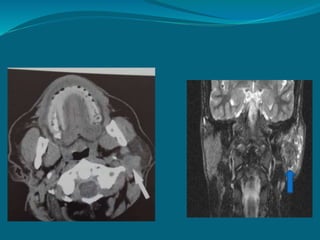

Computer tomography

 Useful for evaluating salivary

gland pathology,adjacent

structures and proximity to

facial nerve.

 Calcified structures are

visualized.

 Abscess – hypervascular wall is

evident.

 Definition of cystic walls and

contents.

 Osseous erosions and sclerosis

are visualized.

Sialolith

CT (contrast) images of enlarged

parotid

MRI

 Provides superior soft tissue contrast resolution than

CT.

 Fewer problems with streak artifacts from metallic

dental restoration.

 Image – multiplanar reconstruction software

algorithm.

 iv contrast(gadolinium) – Differentiate cystic & solid